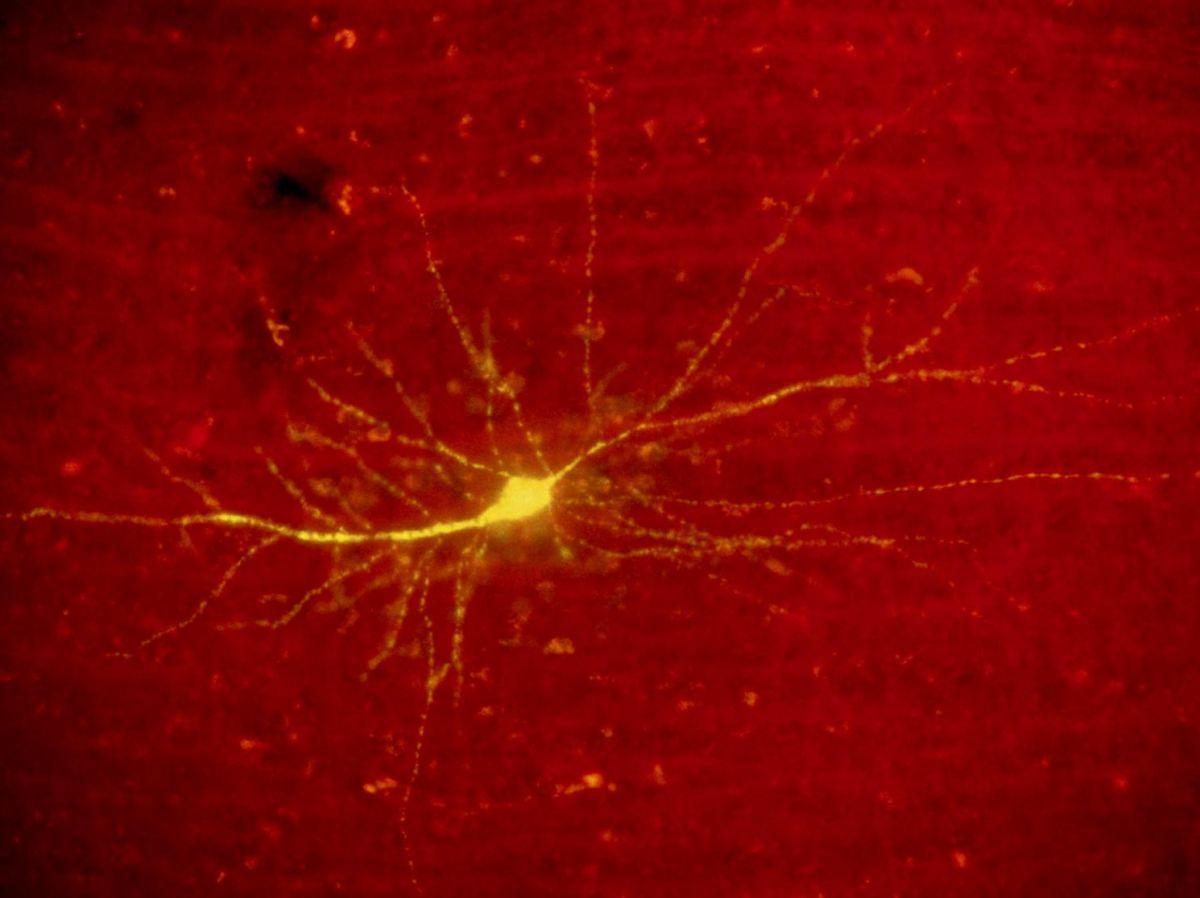

« Depuis environ 20 ans, on savait que l’apprentissage et la mémoire sont accompagnés par des modifications épigénétiques », explique Johannes Gräff. « Mais nous ne savions pas si l’inverse était vrai, si ces modifications peuvent changer la mémoire. » A chaque enregistrement d’un souvenir – on parle d’ »encodage » – des neurones spécifiques à cette information s’activent. Cette population de cellules forme ce que les scientifiques appellent un engramme. Il sera à nouveau activé lorsque le souvenir devra être rappelé.

Dans le laboratoire, les souris sont confrontées à une expérience déplaisante. A un emplacement spécifique de leur cage, elles reçoivent un courant électrique modéré au niveau des pattes. Dans leur cerveau, un engramme encode le souvenir de cette nuisance. Les neurones qui en font partie ont subi des modifications de leur ADN: non pas au niveau de son code, mais de sa structure dans l’espace. Car si l’ADN est souvent représenté sous forme d’une longue chaîne libre ou au contraire compactée sous forme de chromosome en X, sa position dans l’espace est en réalité très variable, selon que les protéines autour desquelles il est enroulé en exhibent ou au contraire en cachent des séquences. Si bien qu’en contorsionnant le brin d’ADN de la bonne façon, deux séquences initialement éloignées peuvent entrer en contact et causer l’activation d’un gène.

Pour beaucoup, ces gènes activés lors de la formation de l’engramme permettent de renforcer la force de la connexion entre les neurones. « Nous réalisons aujourd’hui que l’architecture 3D du génome joue un rôle très important dans l’orchestration de l’expression génétique », concluait dans un communiqué le chercheur Asaf Marco, au sujet de ses travaux publiés en 2020.

Parmi ces gènes activés lors de la formation de l’engramme, c’est au mieux connu ARC que s’intéresse l’équipe de Johannes Gräff. « ARC est un gène extrêmement important pour la plasticité synaptique », c’est-à-dire le remaniement des connexions entre les neurones, justifie le neuroscientifique. Si l’encodage du souvenir du choc électrique repose sur l’activation d’ARC, alors son inactivation pourrait l’effacer, raisonnent les chercheurs.

Et c’est effectivement ce qu’il se passe ! Les scientifiques combinent les ciseaux génétique CRISPR – une protéine capable de repérer l’endroit voulu dans l’ADN – et des enzymes capables d’ouvrir ou de fermer la séquence contenant le gène ARC. Un véritable interrupteur épigénétique créé pour n’agir que dans les neurones de l’engramme du choc électrique qui a été infligé aux souris.